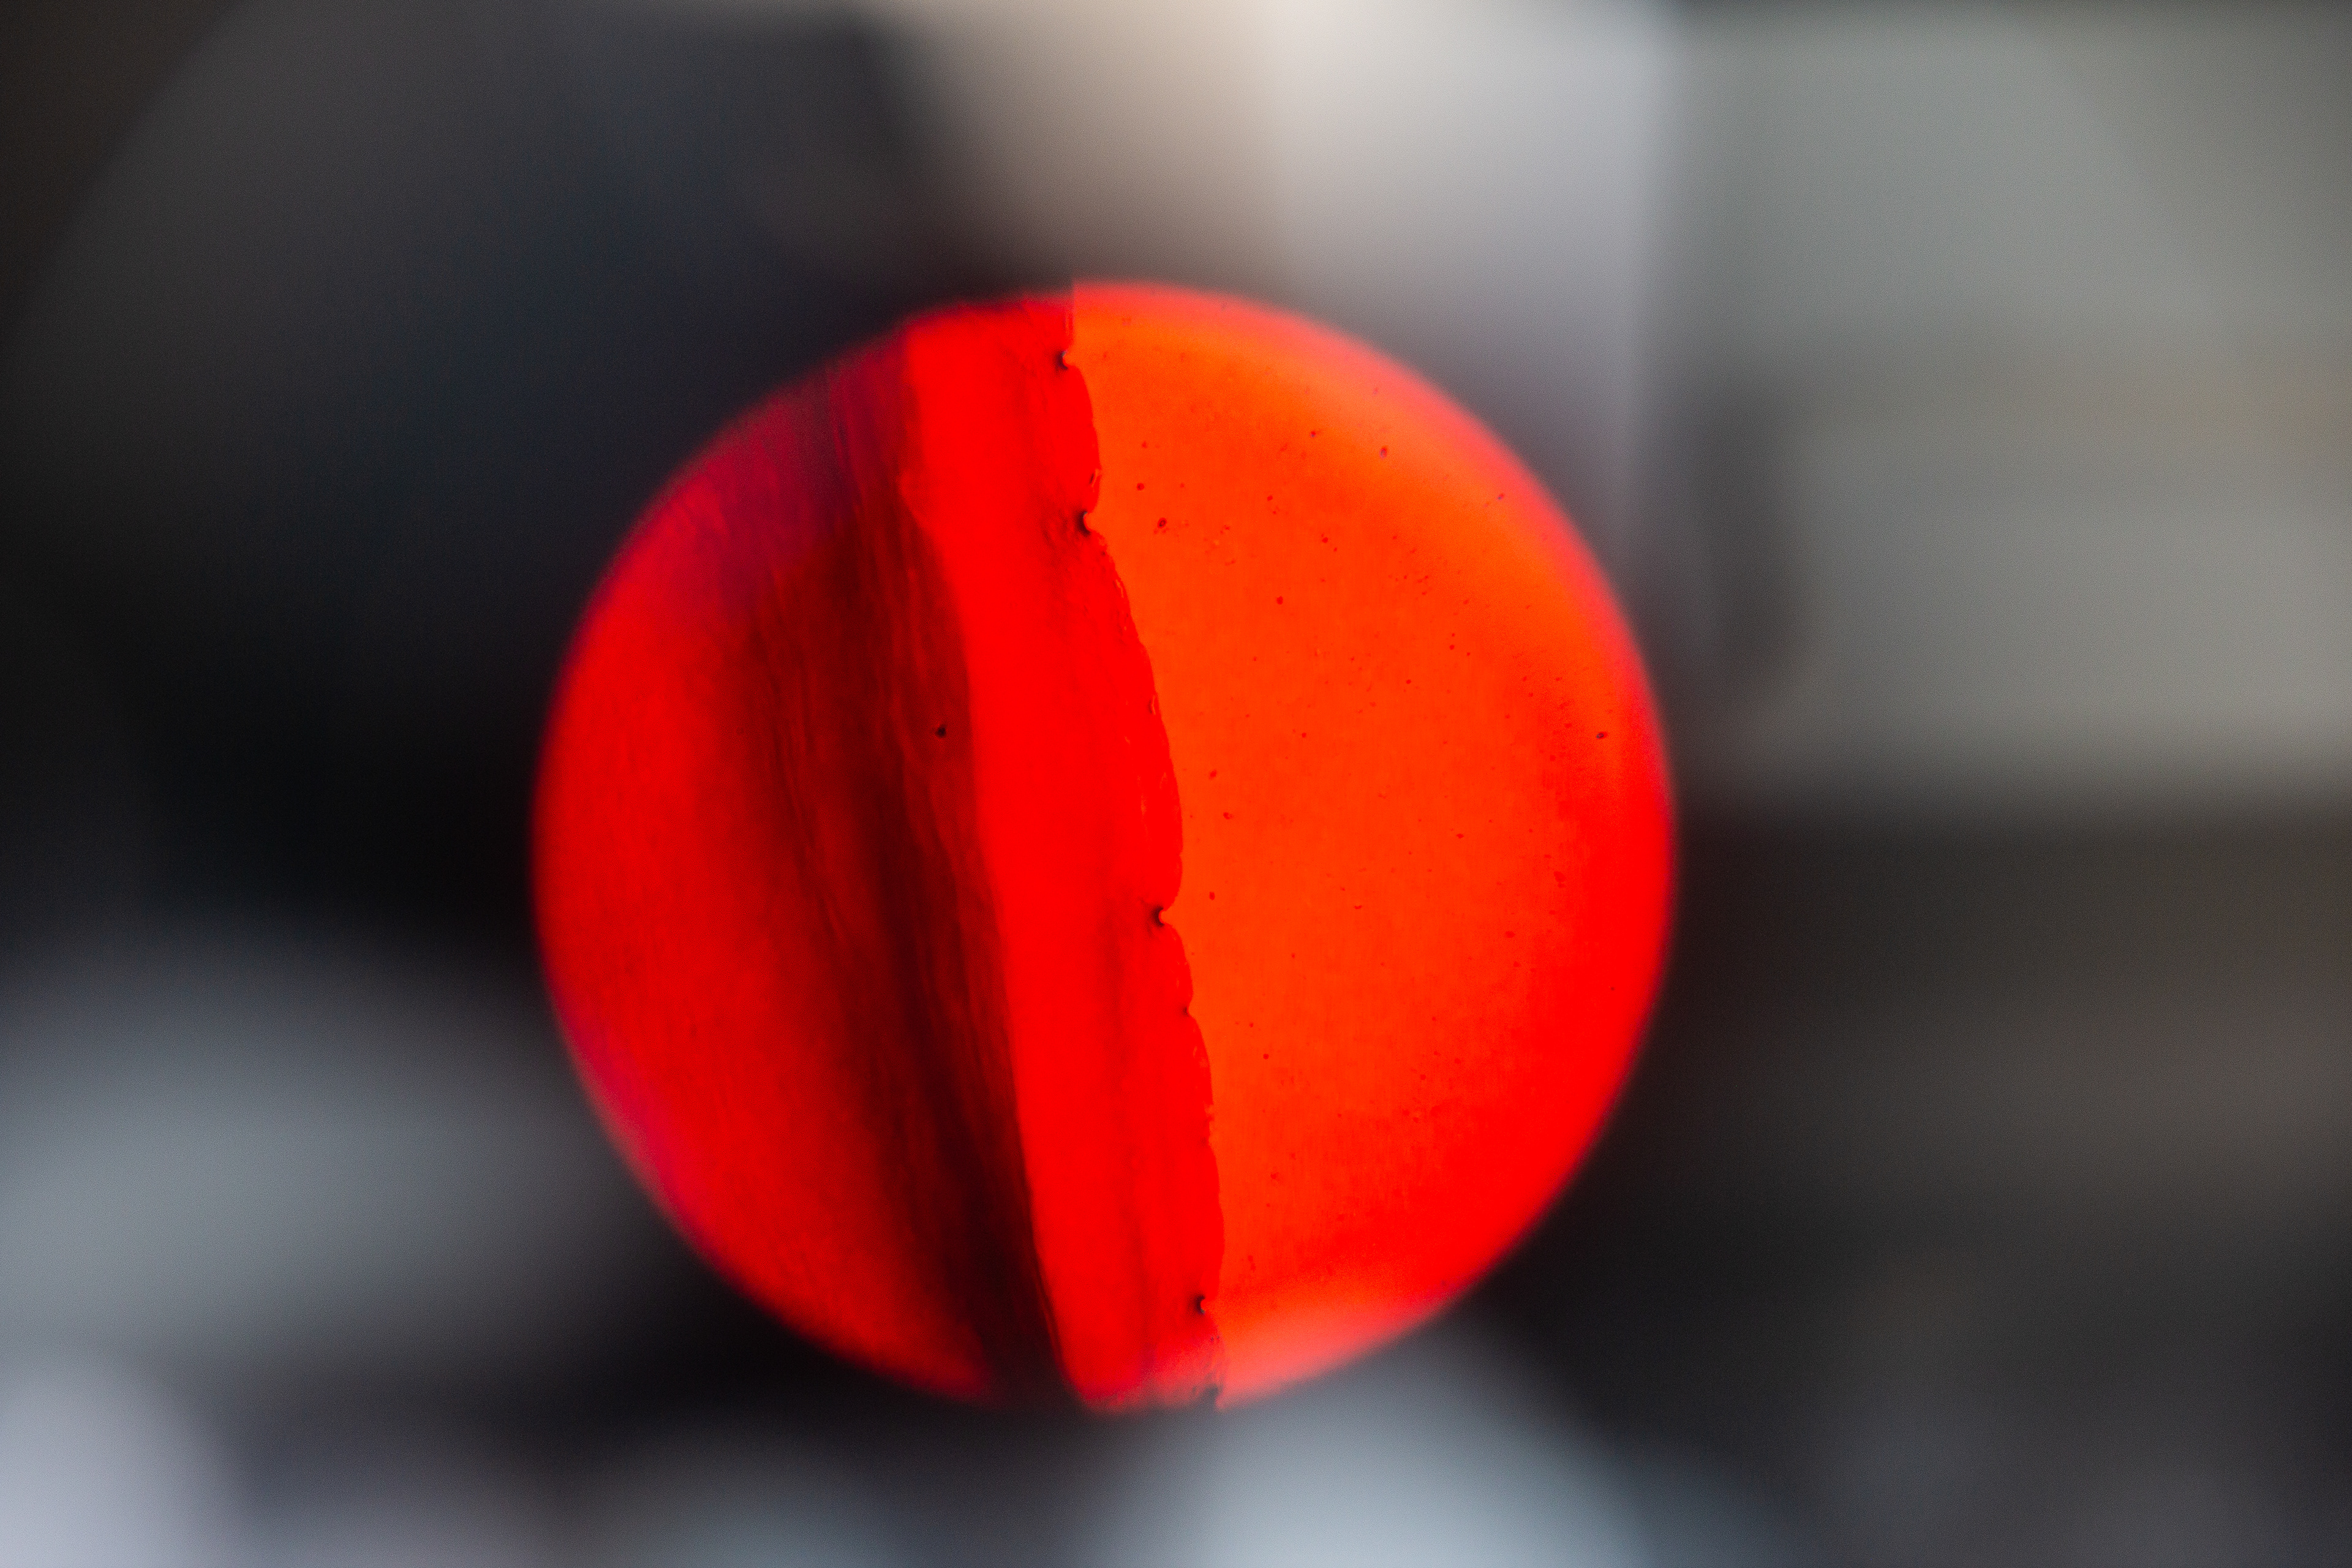

This got me curious. So, I collected and analyzed my own menstrual blood. First I took a look at my venous blood from my small finger and then compared it to my menstrual blood. The following pictures show my menstrual blood at different magnifications:

Menstrual Blood 100x